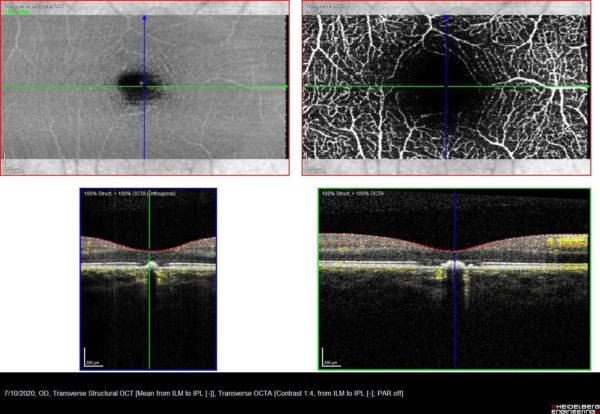

On examination, best-corrected visual acuity (BCVA) was 7/10 in the right eye and 10/10 in the left. Anterior segment and intraocular pressures were normal in both eyes. Fundoscopy revealed a round, well-defined deep yellowish-orange discoloration at the level of the retinal pigment epithelium (RPE) in the right foveola, with no evidence of fluid or retinal hemorrhage (Figure 1). Structural spectral-domain optical coherence tomography (SD-OCT) showed a hyperreflective lesion at the right fovea, with disruption of the overlying ellipsoid zone (Figure 2). Fundus autofluorescence and fundus fluorescein angiography were unremarkable. Optical coherence tomography angiography (OCT-A) revealed a hypointense lesion in correspondence with the focal hyperreflectivity detected on structural OCT, suggesting rarefaction of the choriocapillaris (Figure 3).

Figure 3: Optical coherence tomography angiography (OCT-A) demonstrating a hypointense lesion at the choriocapillaris segmentation, in correspondence with the focal hyperreflectivity detected on structural OCT (lower row, blue arrows), suggesting rarefaction of the choriocapillaris (upper row, red arrows).